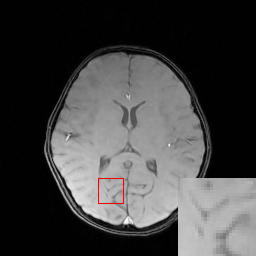

We evaluate the proposed DECN framework using PSNR and SSIM (structural similarity index) [30] as quantitative image quality assessment measures. We give the quantitative reconstruction results of all the test data on different under-sampling patterns and different under-sampling ratios in Table II. We show the Cartesian 30%percent3030\% under-sampling mask in Figure 6(b) and the Random 20%percent2020\% under-sampling mask in Figure 7(b). We observe that DECN improved all off-the-shelf CS-MRI inversion methods on all the under-sampling patterns. Since the Random mask enjoys the more incoherence than the Cartesian mask with the same under-sampling ratio, the CS-MRI achieves better reconstruction quality on the Random masks. Also, we observe the plain DC-CNN model already achieves good reconstruction accuracy, leaving less structural errors for the error correction module, leading to the limited performance improvement about 0.1 dB on the Random 20%percent2020\% and 30%percent3030\% masks. While for other CS-MRI inversions on various sampling patterns, the improvements are at least 1.5dB or even up to 3.5 dB.

In Figure 6, we show reconstruction results and the corresponding error images of an example from the test data on the 1D 30%percent3030\% under-sampling mask. With local magnification on the red box, we observe that by learning the error correction module, the fine details, especially the low-contrast structures are better preserved, leading to a better reconstruction.

Figure 6: We show the reconstruction results of our DECN model with local area magnification. We also show the reconstruction error for our DECN model under different guide module in the last row.